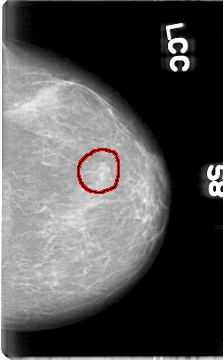

D_4080_1.LEFT_CC

LEFT_CC LINES 5386 PIXELS_PER_LINE 3331 BITS_PER_PIXEL 12 RESOLUTION 43.5 OVERLAY

FILE: D_4080_1.LEFT_CC.OVERLAY

TOTAL_ABNORMALITIES 1

ABNORMALITY 1

LESION_TYPE MASS SHAPE OVAL MARGINS OBSCURED

ASSESSMENT 0

SUBTLETY 5

PATHOLOGY BENIGN

TOTAL_OUTLINES 1

BOUNDARY